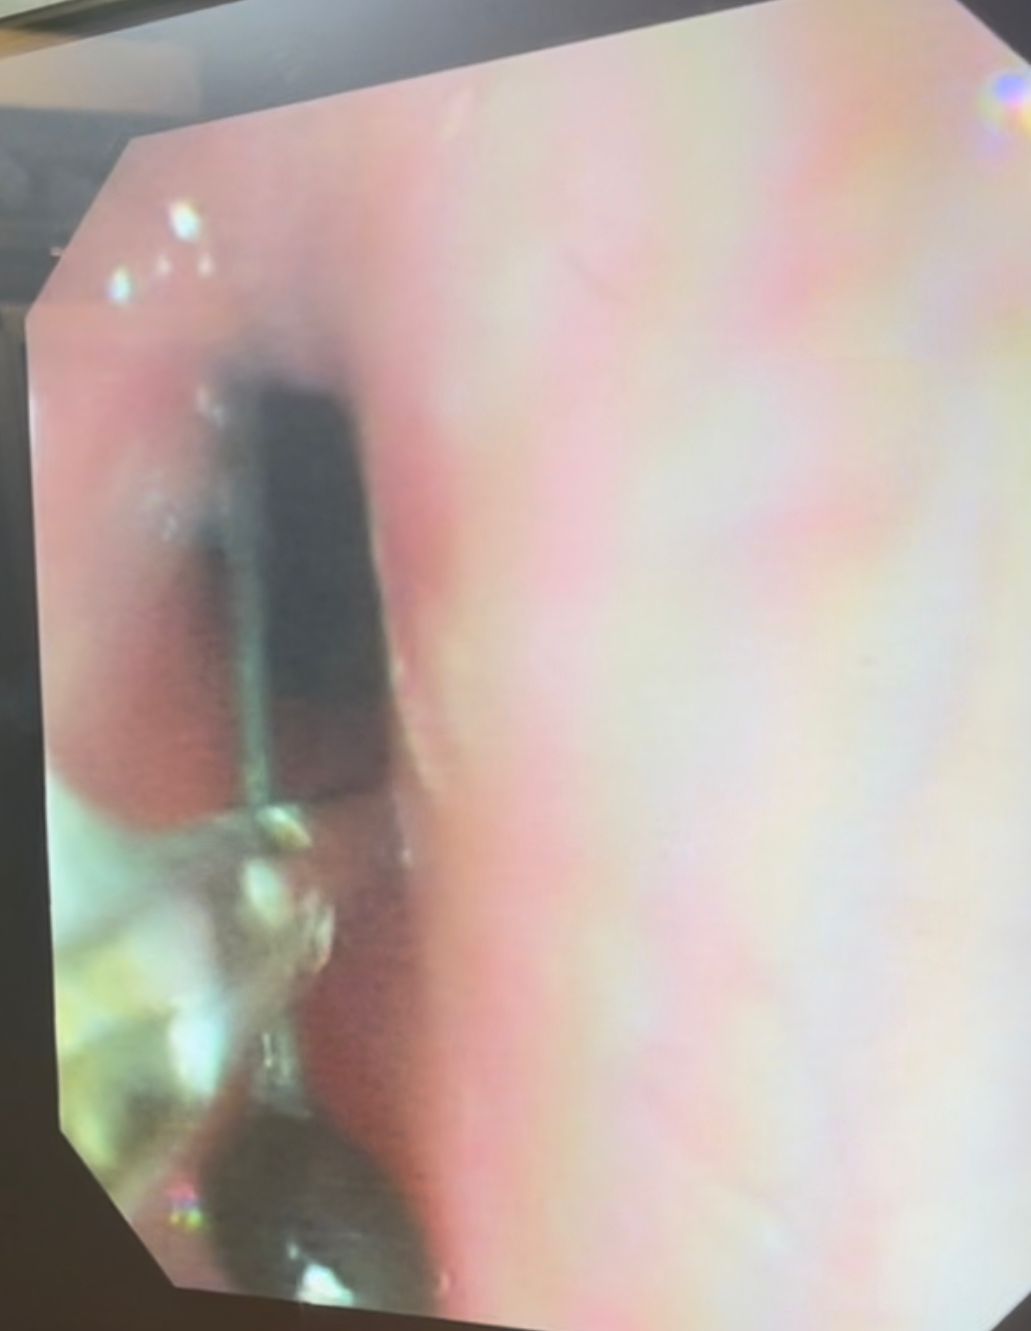

نجح فريق طبي من وحدة أمراض الجهاز الهضمي والكبد ومناظير الأطفال بقسم طب الأطفال بمستشفى سوهاج الجامعي في إجراء تدخل دقيق لاستخراج دبوس من معدة صغير يبلغ من العمر 4 سنوات، باستخدام منظار معدة خاص بالأطفال، دون حدوث أي مضاعفات، وغادر الطفل المستشفى بعد ثلاث ساعات فقط من الإجراء، وهو في حالة صحية جيدة.

وأكد الدكتور أحمد كمال، المدير التنفيذي للمستشفيات الجامعية، أن التعامل مع الحالة تم بسرعة وكفاءة، حيث تمكن الفريق الطبي من استخدام المنظار الخاص بالأطفال لاستخراج الدبوس دون أي تدخل جراحي، مما ساهم في خروج الطفل من المستشفى في نفس اليوم بحالة ممتازة.